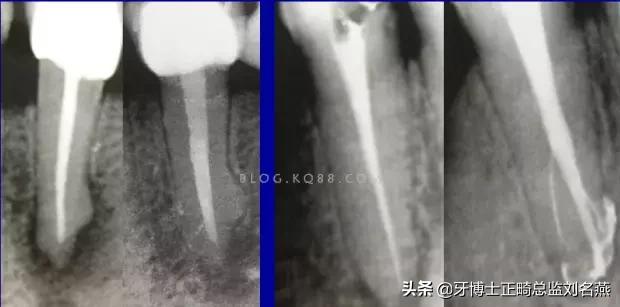

一个牙齿的根管治疗难易程度不单单是根管的弯曲、细小、牙位、是否再治疗决定的,开髓的直线进入和根管口的预先恰当处理可以简化很大的难度,开髓是根管成败的基础。

对于弯曲根管冠部的直线入口就显得尤为重要,冠部良好的直线入口可以避免侧穿、台阶、遗漏根管等问题的发生,冠部直线入口形成的良好情况,取决于医生的理念和合理的器械选择。开髓孔的大小不是由医生和患者的意愿决定的,而是由要治疗牙齿的髓腔大小决定的。